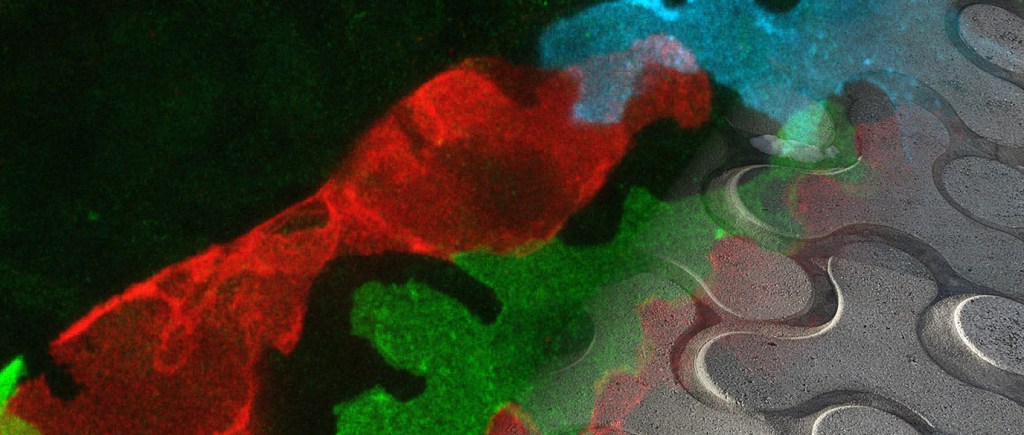

Recent research has highlighted the remarkable heterogeneity of the vascular system, composed of both the blood and lymphatic vasculatures. These systems vary significantly across organs, with differences in morphology, function, and developmental origin. In particular, the lymphatic system has emerged as an important organ-specific regulator of tissue homeostasis, extending beyond its traditional role in fluid drainage to active shaping local immune responses through modulation of adaptive immunity. Moreover, lymphatic endothelial cells (LECs) produce paracrine (lymphangiocrine) factors that regulate organ growth and regeneration. The growing recognition of the diverse functions of the lymphatic system in important physiological processes and disease conditions, such as autoimmune disease and atherosclerosis, highlights the need for a better understanding of the underlying mechanisms.